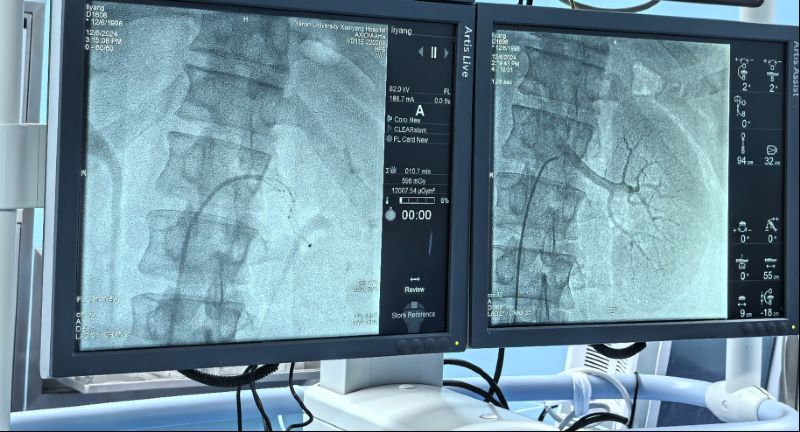

術(shù)中通過對左右腎動脈造影,了解腎動脈解剖結(jié)構(gòu)、評估腎臟灌注情況。而后順利將射頻消融導(dǎo)管的電極頭推至腎動脈主干及分支中遠段,雙側(cè)腎動脈累計消融16次,涵蓋相應(yīng)分支及主干,共完成78個有效消融點,完成后再次行雙腎動脈造影,評價手術(shù)對腎動脈形態(tài)和腎血流影響,累計用時僅60分鐘高效圓滿完成。術(shù)前血壓由154/110mmHg,手術(shù)完成后血壓130/94mmHg,即刻血壓下降效應(yīng)明顯,直至目前術(shù)后減少三種降壓藥物,監(jiān)測血壓維持在120/70mmHg左右,手術(shù)效果理想,長期血壓下降情況我們將持續(xù)隨訪關(guān)注。